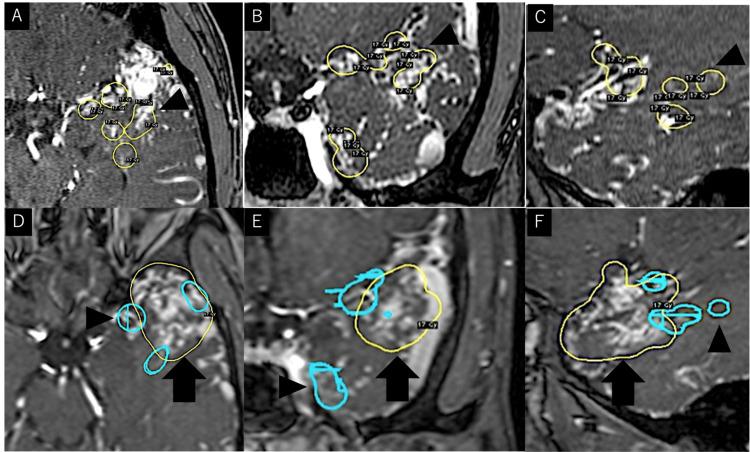

We report the case of a 29-year-old man who presented with a sudden headache. Computed tomography showed a small intraventricular hemorrhage in the left lateral ventricle. Cerebral angiograms suggested rupture of a coexisting feeder aneurysm in the left temporal cerebral arteriovenous malformation (AVM). The left proximal middle cerebral artery, a major feeding artery, was occluded near the AVM, with development of abnormal blood supply, such as in moyamoya-like vessels to the nidus. After endovascular embolization of the coexisting feeder aneurysm and feeding arteries, the patient underwent volume-staged Gamma Knife radiosurgery (GKS). Follow-up angiograms performed 4.5 years after the last GKS confirmed complete disappearance of the AVM. Around 4.8 years after GKS, the patient required surgical intervention to develop delayed cyst formation; however, the postoperative course was uneventful.